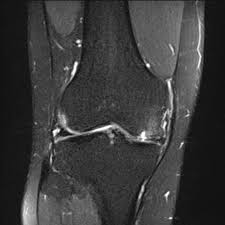

Medial Femoral Condyle Chondromalacia : Chondromalazie Stockfotos Und Bilder Kaufen Alamy, Can chondromalacia patellae be cured by conservative treatment avoiding surgery?. Osteonecrosis, or bone death, of the medial femoral condyle is treated either through nonsurgical or surgical methods, the hospital for special surgery explains. Pattern typical of grade i chondromalacia. The optimum location for the fam portal during acl reconstruction should avoid cartilage damage to the medial femoral condyle. The purpose of this trial is to evaluate the safety and effectiveness of the biphasic cartilage repair implant (bicri) compared to marrow stimulation in the treatment of chondral and osteochondral lesions located on the medial femoral condyle, lateral femoral condyle, or trochlea of the knee. Although extensive marrow edema is present, there is only mild to moderate chondromalacia at the medial femoral condyle, and no meniscal tear.

Moving the insertion of the quadriceps tendon medially at the tibial. Although extensive marrow edema is present, there is only mild to moderate chondromalacia at the medial femoral condyle, and no meniscal tear. Find specific details on this topic and related topics from the msd vet manual. Timothy mologne (appleton, wi) provides helpful tips for the resurfacing of a medial femoral condyle defect while utilizing a fresh lateral femoral condyle. Of the upper medial femoral condyle (same as for the talus.